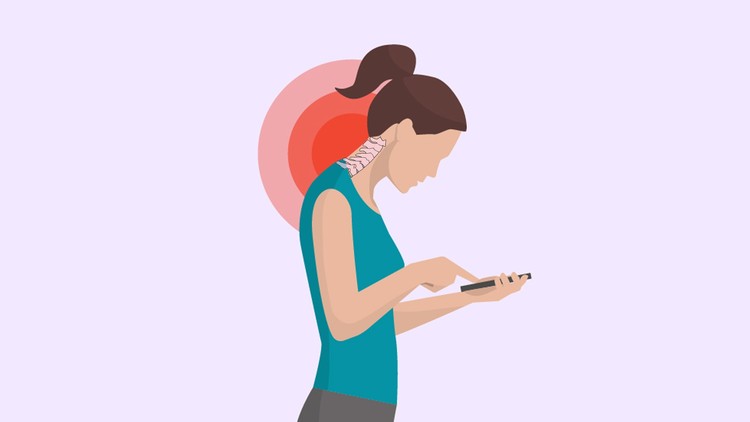

3- Suffering from text neck.

Your neck muscles, tendons and ligaments are forced forward when you text causing a strain. Texting 24/7 is a very unhealthy habit and you need to get rid of it, the sooner the better. You will start noticing positive changes.